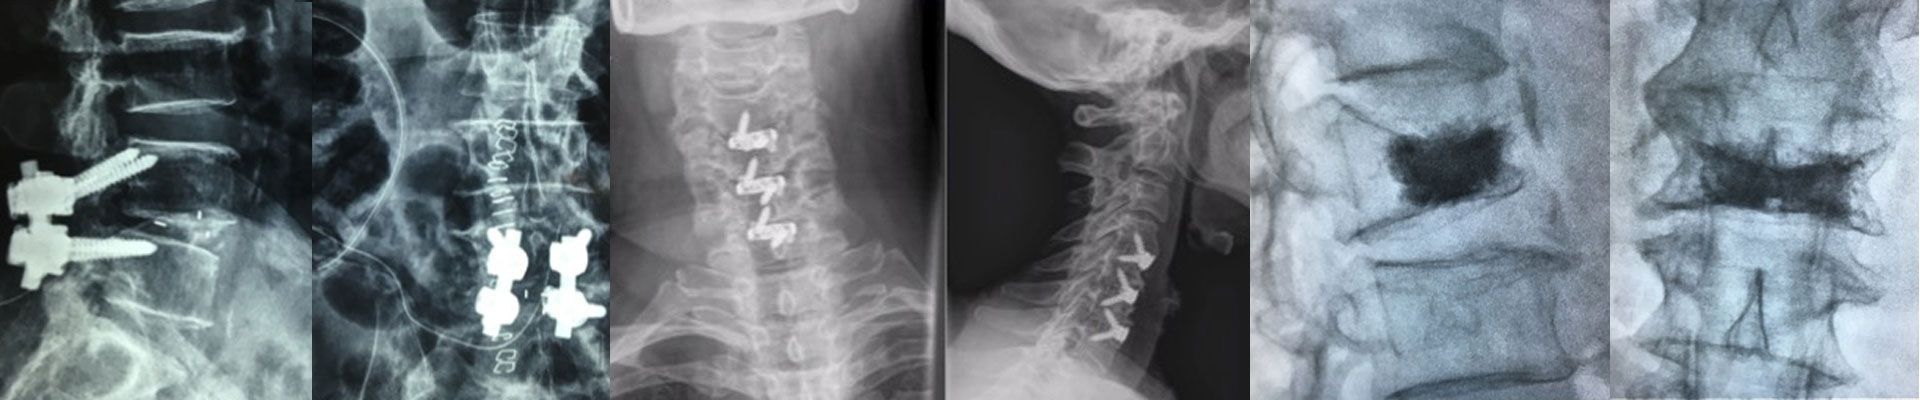

Anterior Cervical Discectomy and Fusion

Cervical TB and Corpectomy

Spondylolisthesis

Spondylolisthesis & Minimally Invasive Transforminal Interbody Fusion

Vertebroplasty

Vertebroplasty / Vertebral body stenting